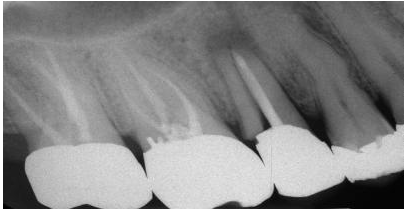

圖1:上頜第二前磨牙根折的根尖片,經(jīng)由預(yù)成金屬樁修復(fù)

大多數(shù)牙髓治療的后牙都必須進(jìn)行牙冠修復(fù)以增強(qiáng)其行使功能的時(shí)間。臨床實(shí)踐中,口腔醫(yī)生已經(jīng)觀(guān)察到牙髓治療后的牙齒與活髓牙之間的不同之處。與活髓牙相比,經(jīng)過(guò)牙髓治療的牙齒更容易劈裂;在拔牙過(guò)程中無(wú)髓牙更容易折斷,未經(jīng)牙冠修復(fù)的無(wú)髓磨牙更傾向于劈裂。